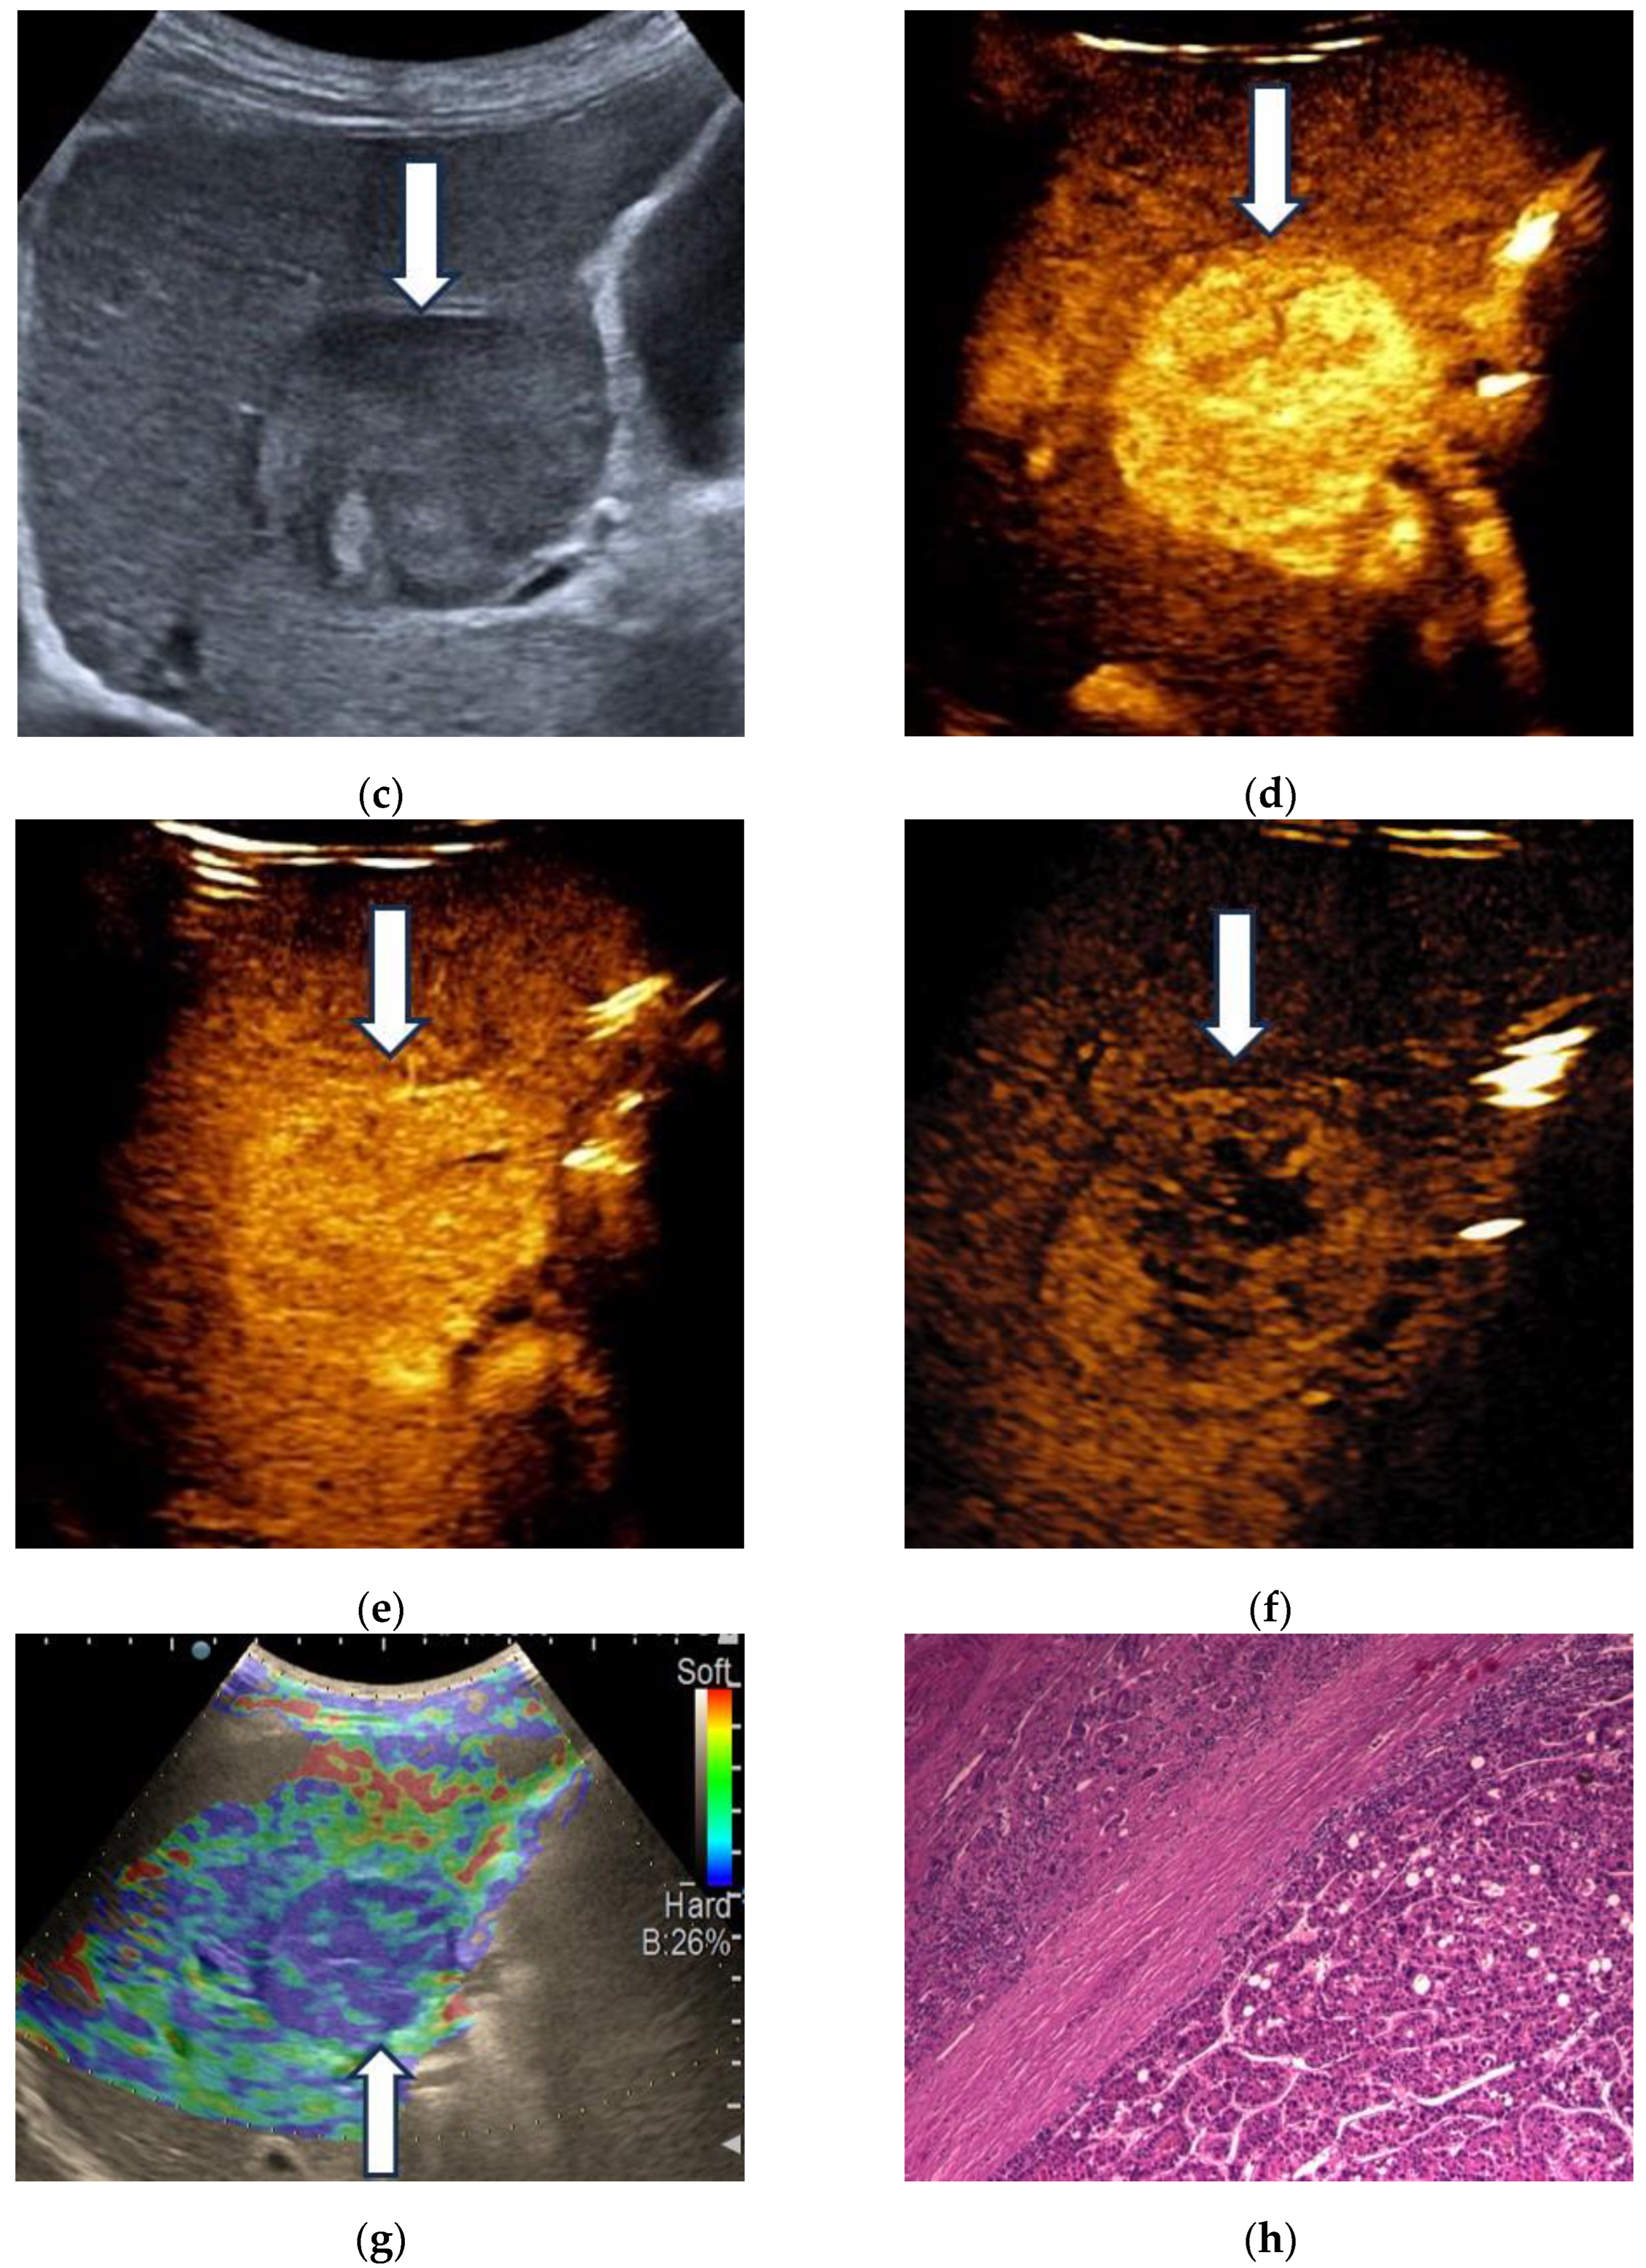

3.2. Contrast-Enhanced Ultrasound

3.3. Shear Wave Measurements in Liver Tumors

3.4. Real-Time Tissue Elastography